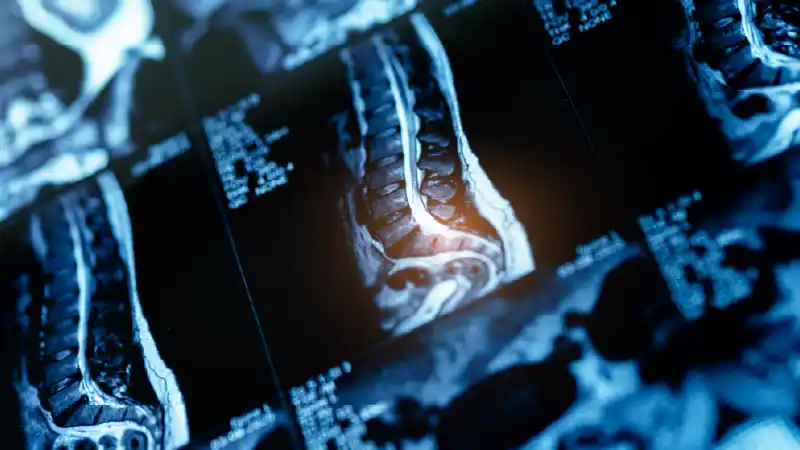

What is a Spinal MRI?

MRI of the spine is a test that uses a combination of radio waves, a large magnetic field and a computer to create detailed images of the spine and surrounding tissues.

MRI scans are broadly done to know the exact reason behind back pain, numbness or weakness. It is known as the most accurate and effective forms of medical imaging that is available worldwide. MRI scan help in providing both patients and doctors with a valuable information about their health. Additionally, it helps health professionals to diagnose their condition more accurately.